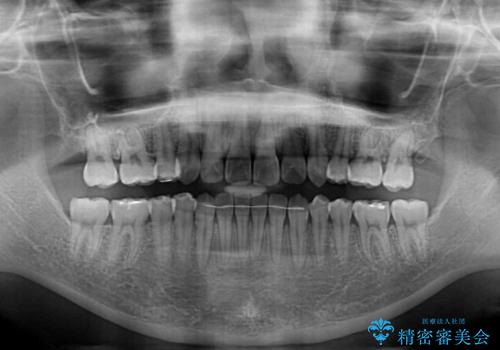

上下の前歯が非接触であり、叢生や八重歯が顕著であったため、上顎左右第一小臼歯2本を抜歯して排列することとしました。

抜歯により移動量が多くなるため、ワイヤーや補助装置を活用し、その後インビザラインによる矯正治療を行うこととしました。

元々奥歯に負担のかかる咬み合わせですり減っていたため、仕上がった歯並びでも奥歯が咬んでいないように見えましたが、実際にはしっかりと咬合しており、患者様本人も咬んだ感触に違和感はないとのことでした。